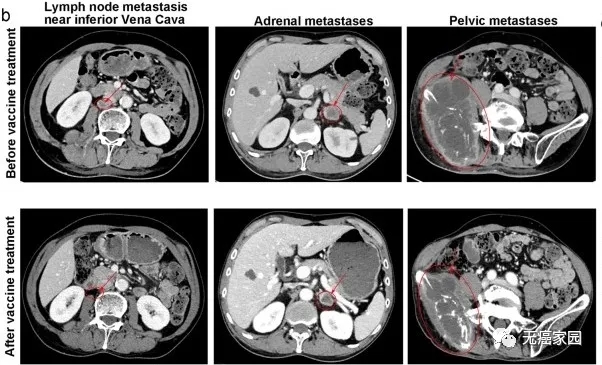

图中患者靠近下腔静脉的转移瘤基本消失,肾上腺转移及盆腔巨大转移灶明显缩小

患者25,具有EGFR ΔEx19肿瘤,使用纳武单抗出现进行性转移,随后对采用TILs治疗后达到完全缓解。随着时间的推移,通过代表性对比增强轴向 CT图像显示放射学目标病变的总和。

患者09是一位患有肺腺癌的前吸烟者。10个月后,她获得了纳武单抗PR(部分缓解),随后转移淋巴结肿大,新的活检证实肋骨软组织转移。然后她接受了TIL治疗,并且获得了CR(完全缓解),同时放射学目标病变持续缺失。随着时间的推移,显示了代表性的冠状对比增强CT图像。